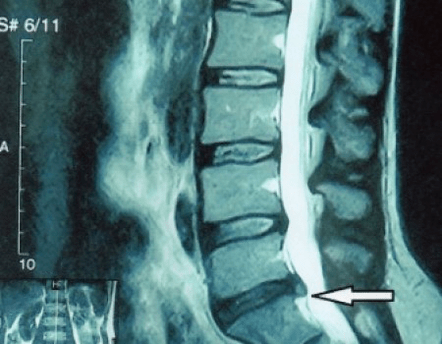

Μια «ακτινογραφία» της αυχενικής μοίρας της σπονδυλικής στήλης και ακόμη και οι λειτουργικές εξετάσεις για κάμψη και επέκταση δεν δείχνουν χόνδρο επειδή ο ιστός του επιτρέπει στις ακτίνες Χ να περάσουν. Ωστόσο, με βάση τη θέση των σπονδύλων, μπορεί κανείς να συναγάγει γενικά συμπεράσματα για το ύψος των μεσοσπονδύλιων δίσκων, τη γενική ανόρθωση της φυσιολογικής καμπυλότητας του αυχένα - λόρδωση - καθώς και την παρουσία οριακών αυξήσεων στους σπονδύλους με παρατεταμένο ερεθισμό των επιφανειών τους από εύθραυστα και αφυδατωμένα μεσοσπονδύλια δισκάκια. Οι λειτουργικές εξετάσεις μπορούν να επιβεβαιώσουν τη διάγνωση της αστάθειας της αυχενικής μοίρας της σπονδυλικής στήλης.

Δεδομένου ότι οι ίδιοι οι μεσοσπονδύλιοι δίσκοι είναι ορατοί μόνο με αξονική τομογραφία ή μαγνητική τομογραφία, η μαγνητική τομογραφία και η αξονική τομογραφία ακτίνων Χ ενδείκνυνται για την αποσαφήνιση της εσωτερικής δομής του χόνδρου και των σχηματισμών όπως εξογκώματα και κήλες. Έτσι, με τη βοήθεια αυτών των μεθόδων γίνεται ακριβής διάγνωση και το αποτέλεσμα της τομογραφίας αποτελεί ένδειξη και μάλιστα πραγματικό οδηγό για τη χειρουργική αντιμετώπιση μιας βουβωνοκήλης στο νευροχειρουργικό τμήμα.